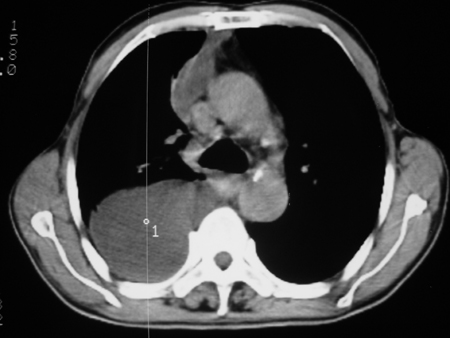

男77岁,胸痛就诊

右侧胸腔积液,部分包裹,右下肺膨胀不全,右下肺感染。

考虑右肺门占位并下叶不张 右胸包裹积液

右侧胸腔积液,部分包裹,右下肺膨胀不全

右肺中叶及下叶炎症并胸腔积液(部分包裹),建议抽液后复查ct除外占位。